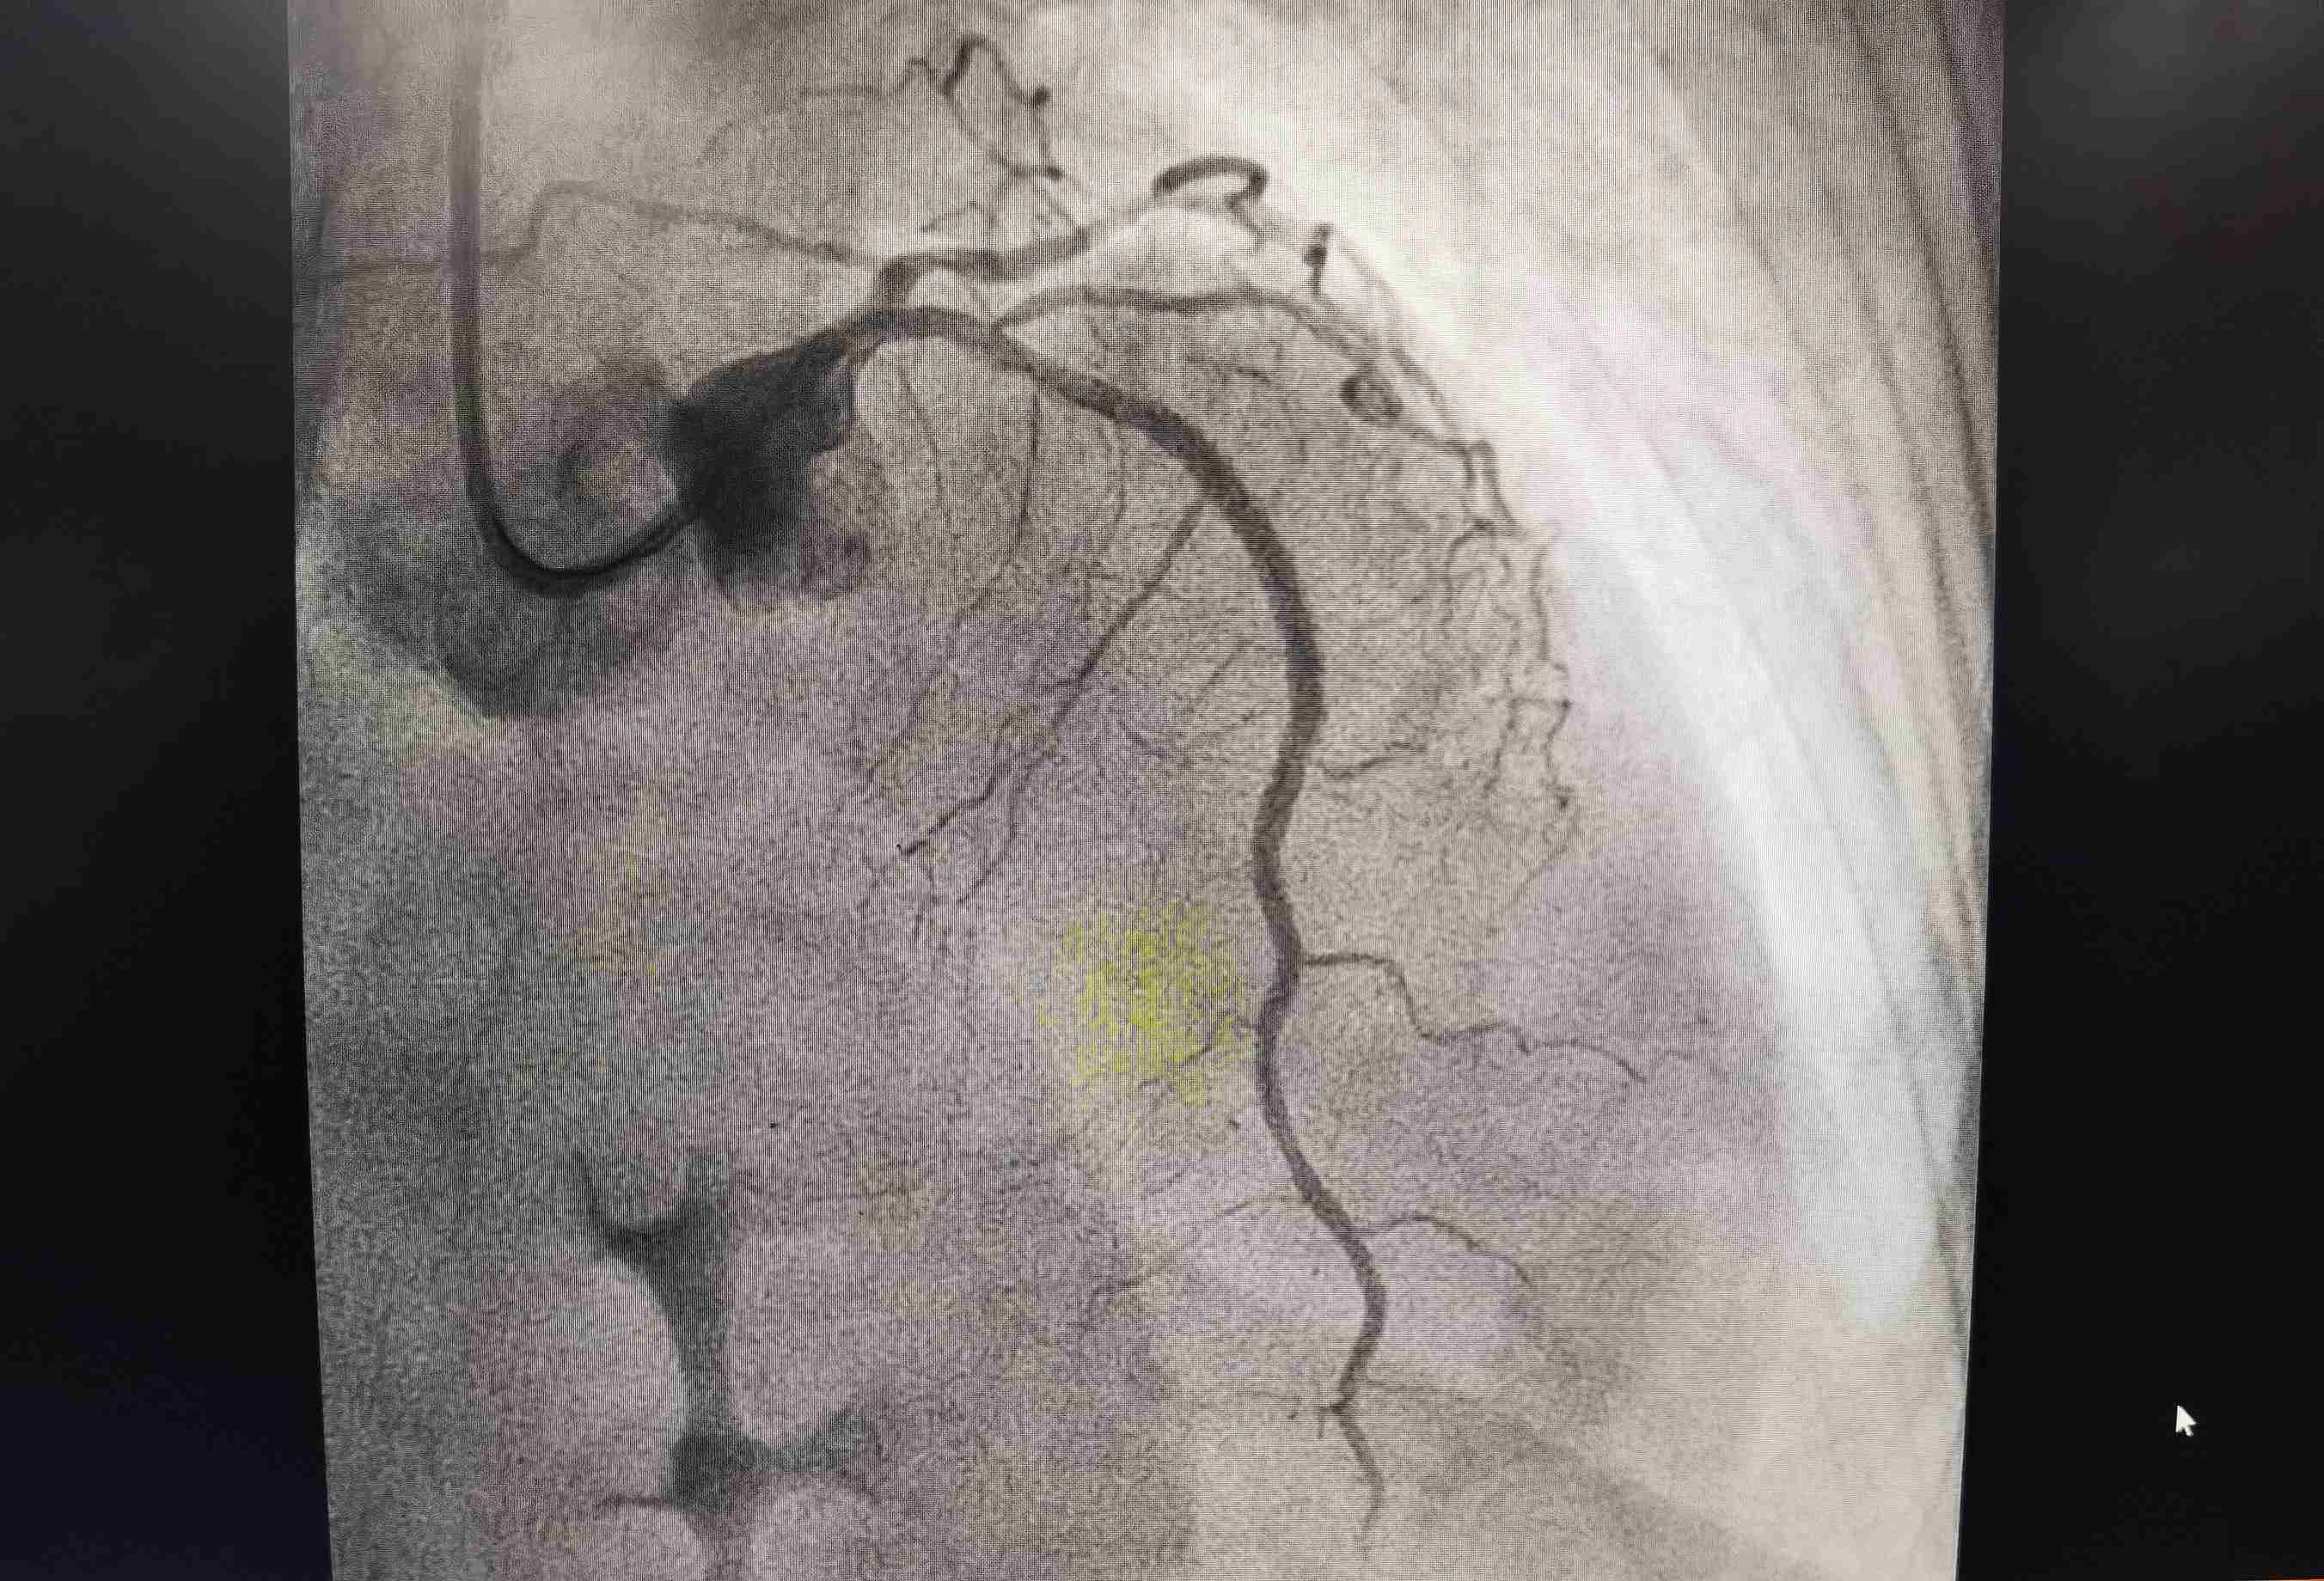

术前血管堵塞造影图片

转诊后,卫生院及时向柳州市人民医院胸痛中心追踪病人的治疗情况,经了解,该患者左前降支近中端次全闭塞、左前降支远端血流TIMI2级、旋支中端狭窄85%、右冠脉近段狭窄60%,置入支架1枚,经过及时救治、患者已转危为安!